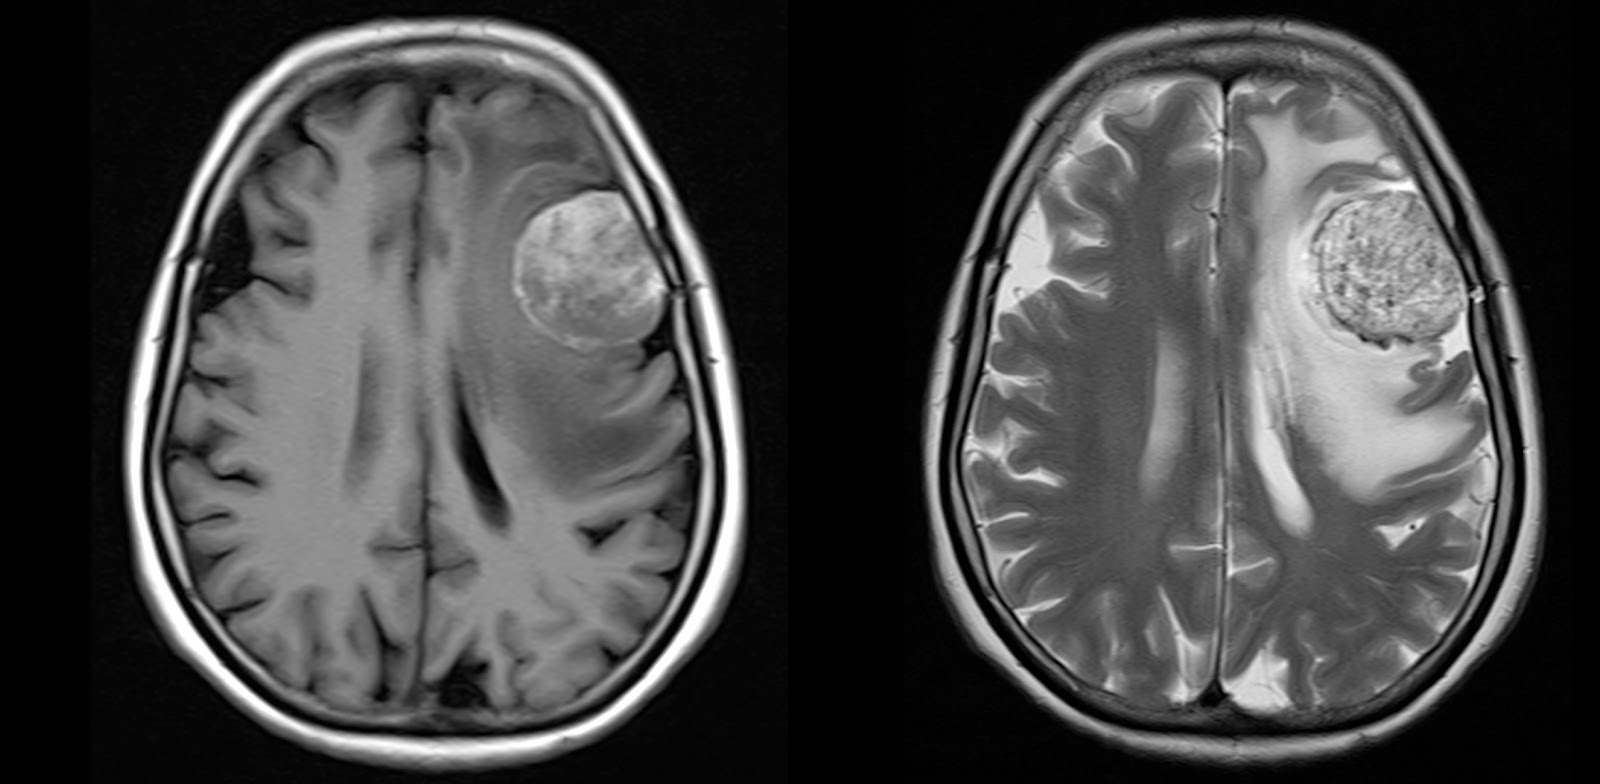

Brain Metastasis Radiology At St Vincent s University Hospital

http://www.svuhradiology.ie/wp-content/uploads/2015/04/BrainMetCombo-894x1024.jpg